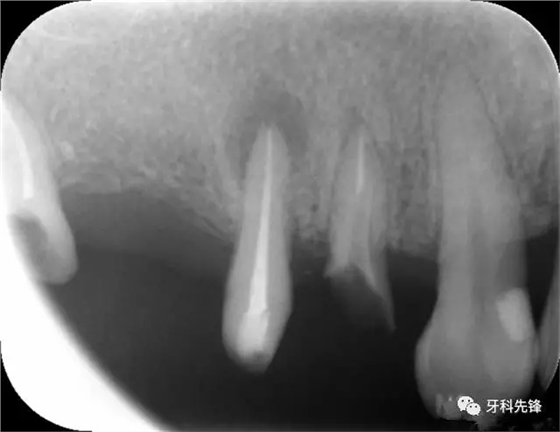

圖1術(shù)前X光片

圖8治療術(shù)后X光片

640.webp (10).jpg

640.webp (11).jpg

640.webp (12).jpg

圖1814 15 三個(gè)月后X光片(根尖陰影減?。?p style="text-align: left;">640.webp (22).jpg